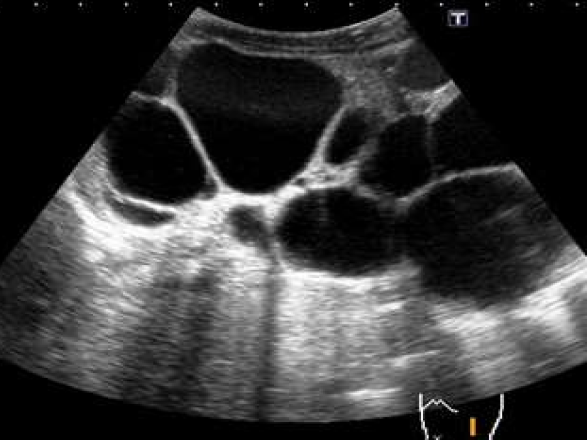

Este sistema se introdujo para proporcionar un enfoque unificado para describir la dilatación del tracto urinario en neonatos y lactantes jóvenes. Se clasifica en tres grados postnatales: UTD P1 (bajo riesgo), UTD P2 (riesgo intermedio) y UTD P3 (alto riesgo). Este sistema ha demostrado ser útil para predecir la necesidad de intervención quirúrgica y la ocurrencia de infecciones del tracto urinario (ITU) en neonatos con hidronefrosis.[1-3]

Este sistema clasifica la hidronefrosis en cuatro grados, de I a IV, basándose en la apariencia ecográfica del sistema colector renal. Los grados más altos están asociados con un mayor riesgo de intervención quirúrgica y menor tasa de resolución espontánea.[4-6]

0, no hydronephrosis / 1) dilatation of renal pelvis alone / 2) plus caliceal dilation / 3)plus< ½ renal parenchymal loss / 4)plus> ½ renal parenchymal loss.